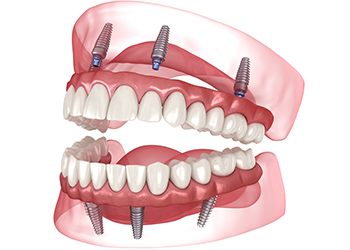

オールオン4(All-on-4)

片顎わずか4本のインプラントで

12本の歯を支えることが可能です

総入れ歯の方や残存歯が少ない方に適した治療方法です。4本(症例によっては6本)のインプラントで最大12本の人工歯を支えることができ、治療本数を抑えることで手術や経済的な負担を軽減できます。通常のインプラントと同様の使用感で、しっかりと咬むことが可能です。あごの骨が痩せている場合でも、手術が行えるケースがあります。

最小4本のインプラントで力を分散し、人工歯をしっかり支えます。必要に応じて本数が増える場合もありますが、従来の治療に比べ、身体的・経済的・時間的な負担を大幅に軽減できます。